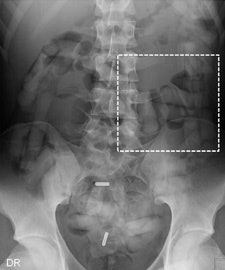

Diagnostic imaging is used to help identify drug smugglers who use their bodies to transport merchandise, and conventional radiography exams have been the standard procedure used for many years. However, it can be difficult for radiologists to detect small capsules on x-ray images.

Abdominal CT scans were overwhelmingly superior to the other modalities, with 100% sensitivity, 94.1% specificity, 94.7% positive predictive value (PPV), and 100% negative predictive value (NPV). This was true for imaging of all three types of suspects: "body packers," who swallow a large amount of packets for gastrointestinal tract passage; "body pushers," who hide drugs in bodily orifices; and "body stuffers," who ingest small amounts of loosely wrapped drug pellets if they suspect that are about to be intercepted.

DR and low-dose linear slit digital radiography exams were less accurate. CT exams had an overall accuracy rate of 97.1%, followed by DR (71.4%, and 60% for low-dose linear slit digital radiography).

Capsules holding cocaine are of different densities. It is important to perform window-level adjustments to detect drug containers, according to the authors. It also helps for a radiologist to know what the typical size and appearance are of different cocaine containers. With this knowledge, they can be better distinguished from normal intestinal gas, calcifications, scybala, and other foreign bodies.